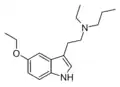

| 5-Ethoxy-DMT | artificial | 5-OCH2CH3 | CH3 | CH3 | 5-ethoxy-N,N-dimethyltryptamine | 855245-09-9 |

| 5-Ethoxy-MET | artificial | 5-OCH2CH3 | CH3 | CH2CH3 | 5-ethoxy-N-methyl-N-ethyltryptamine | |

| 5-Ethoxy-DET | artificial | 5-OCH2CH3 | CH2CH3 | CH2CH3 | 5-ethoxy-N,N-diethyltryptamine | |

| 5-Ethoxy-MPT | artificial | 5-OCH2CH3 | CH3 | CH2CH2CH3 | 5-ethoxy-N-methyl-N-propyltryptamine | |

| 5-Ethoxy-EPT | artificial | 5-OCH2CH3 | CH2CH3 | CH2CH2CH3 | 5-ethoxy-N-ethyl-N-propyltryptamine | |

| 5-Ethoxy-DPT | artificial | 5-OCH2CH3 | CH2CH2CH3 | CH2CH3 | 5-ethoxy-N,N-dipropyltryptamine | |

| 5-Ethoxy-MiPT | artificial | 5-OCH2CH3 | CH3 | CH(CH3)2 | 5-ethoxy-N-methyl-N-isopropyltryptamine | |

| 5-Ethoxy-EiPT | artificial | 5-OCH2CH3 | CH2CH3 | CH(CH3)2 | 5-ethoxy-N-ethyl-N-isopropyltryptamine | |

| 5-Ethoxy-DiPT | artificial | 5-OCH2CH3 | CH(CH3)2 | CH(CH3)2 | 5-ethoxy-N,N-diisopropyltryptamine | |

| 5-Ethoxy-DALT | artificial | 5-OCH2CH3 | H2C=CH-CH2 | H2C=CH-CH2 | 5-ethoxy-N,N-diallyltryptamine | |